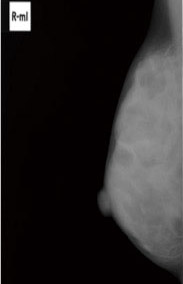

Phương pháp chính để sàng lọc ung thư vú là chụp nhũ ảnh, sử dụng tia X để tạo hình ảnh về tuyến vú. Phương pháp này có thể phát hiện ung thư ở giai đoạn rất sớm mà không thể cảm nhận được bằng tay. Nghiên cứu đã chứng minh rằng xét nghiệm này giúp giảm tỷ lệ tử vong do ung thư vú. Trong quá trình chụp, tuyến vú sẽ bị nén lại bằng một tấm ép, điều này có thể gây khó chịu nhưng cơn đau sẽ giảm nếu bạn giữ tâm trạng thoải mái.

Hình ảnh từ chụp nhũ ảnh cho thấy sự khác biệt giữa ngực dày đặc và ngực bình thường (Ảnh cung cấp: Bà Kinoshita).

Ngực được gọi là “dày đặc” khi chứa nhiều mô tuyến và ít mỡ. Trong hình ảnh chụp nhũ ảnh, cả khối u và mô tuyến đều xuất hiện màu trắng, khiến việc phát hiện ung thư trở nên khó khăn hơn đối với những người có ngực dày đặc. Sau thời kỳ mãn kinh, mô tuyến thường được thay thế bằng mỡ và mật độ mô giảm đi; tuy nhiên, vẫn có nhiều phụ nữ duy trì mật độ cao sau khi mãn kinh. Do đó, bạn nên hỏi bác sĩ về tình trạng của mình trong quá trình kiểm tra sức khỏe.